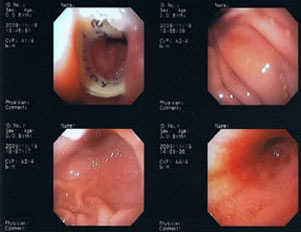

11歳 ミニチュア・ダックス 去勢オス

主訴:焼き鳥の竹串を食べたとの事で来院しました。元気・食欲は問題なく、嘔吐などの症状もありませんでした。便にも竹串が1/3程でているとの事でしたが、全ての竹串が出ていないため、内視鏡検査を実施致しました。

内視鏡検査所見:胃内に竹串の先端部分が残っていたため、異物鉗子にて摘出しました。胃内は、全体的に炎症を伴い、出血している部位も確認されました。摘出後は、胃粘膜保護薬・プロトンプインヒビター(胃薬)の内服2剤ならびに食事療法により経過は良好です。

内視鏡下写真

◎竹串誤飲は、異物の1位と言われるほど多く認められています。竹串は、先端が尖っているため消化管穿孔などを起こし、命に関わることもあります。万が一、ご自宅や散歩中に串などを食べてしまった場合は、病院まですぐご連絡下さい。また竹串は、食道を傷つけ・穴をあける恐れなどもあるため無理に吐かせる事は絶対にしないで下さい。本症例は、内視鏡下にて摘出が可能でしたが、状況によっては開腹が必要となる場合もあります。